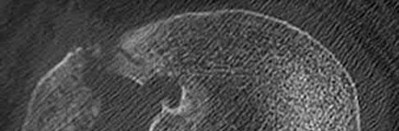

3. # Which of the following is not an appropriate implant for treatment of the fracture seen in Figure A?

The image shows a reverse obliquity intertrochanteric hip fracture.

According to the referenced article by Haidukewych et al, unstable peritrochanteric hip fractures have a worse outcome (failed in 9/16 cases) if treated with a sliding hip screw. Two additional factors that were found to have a strong correlation with postoperative failure (nonunion, loss of reduction) were poor reduction and poor implant placement. In this study, fixed angle devices were superior. Intramedullary fixation has the added advantage of a shorter lever arm and less potential for fracture collapse and limb shortening.

The IMN also acts as a medial buttress.

According to Sanders et al, the dynamic condylar screw (DCS) can also be used in subtrochanteric models, but should not be used if extensive comminution is seen, as they reported a high failure rate with DCS in these fractures if highly comminuted. They report a 77% overall union rate with this device.